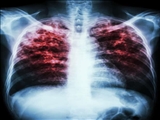

کلیه خدمات تشخیص و درمان بیماری سل رایگان است

رئیس مرکز بهداشت شهرستان مراغه:

رئیس مرکز بهداشت شهرستان مراغه گفت: کلیه خدمات تشخیص و درمان بیماری سل در تمامی مراکز بهداشتی شهرستان رایگان بوده و ساده ترین راه تشخیص این بیماری انجام آزمایش خلط در سه نوبت است.